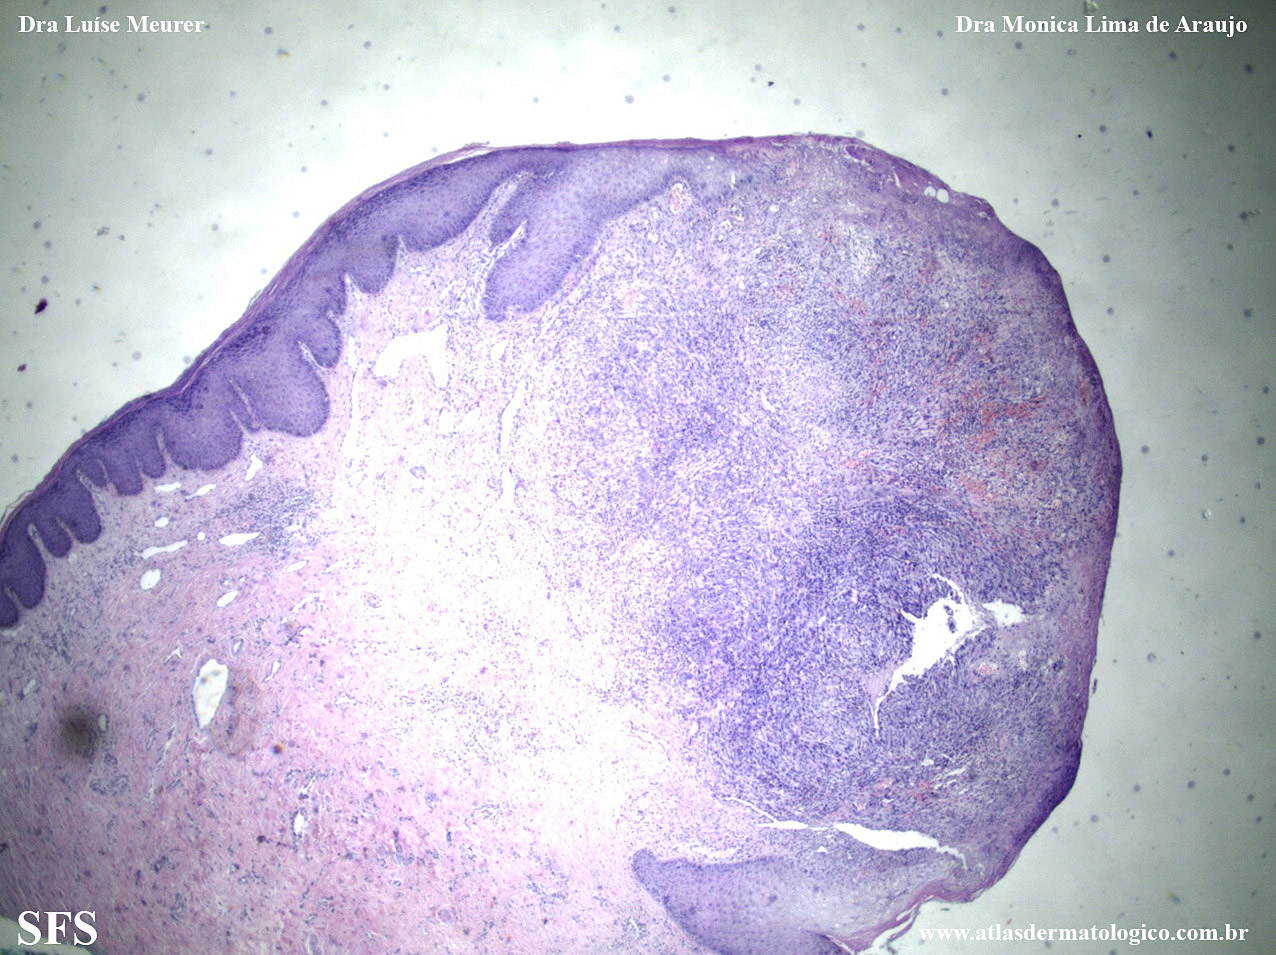

kaposi's _sarcoma_associated_herpesvirus_type_8